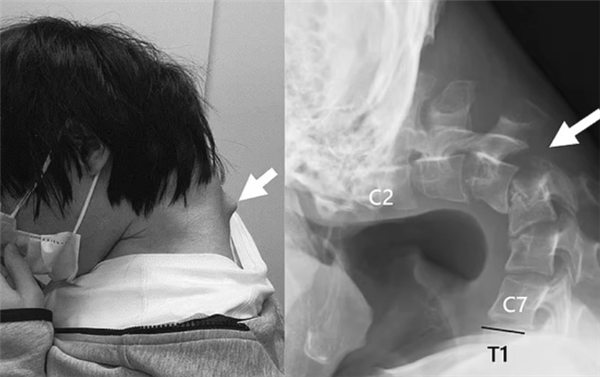

• 日本25岁男子沉迷手游致脖子长角:无法抬起头 出现吞咽困难

电脑知识网5月16日消息,据媒体报道,日本医疗团队近日报告了一例特殊的"下垂头综合症"病例。 一名25岁男性患者因长期保持低头姿势玩手机游戏,导致颈部椎骨严重变形,在颈椎处形成了一个明显的异常包块。医学检查显示,其颈椎因长期处于不自然位置而出现"极度伸展"的病理改变。 该患者不仅遭受着剧烈的颈部疼痛,甚至丧失了自主抬头…